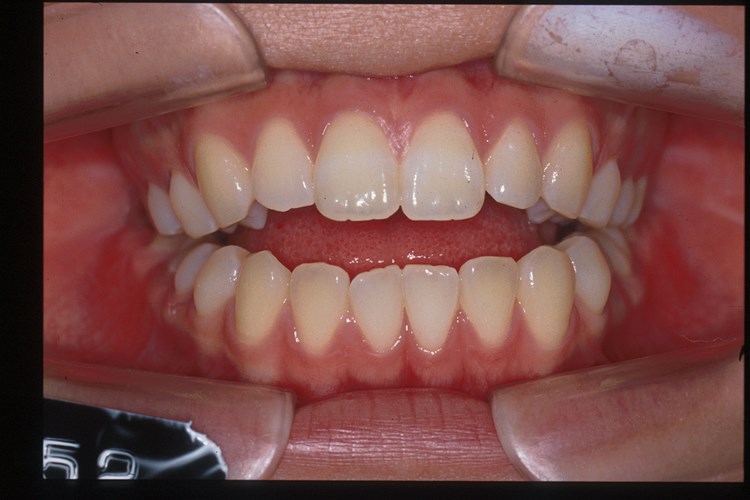

表側からの矯正正 面

Before

After右側貌